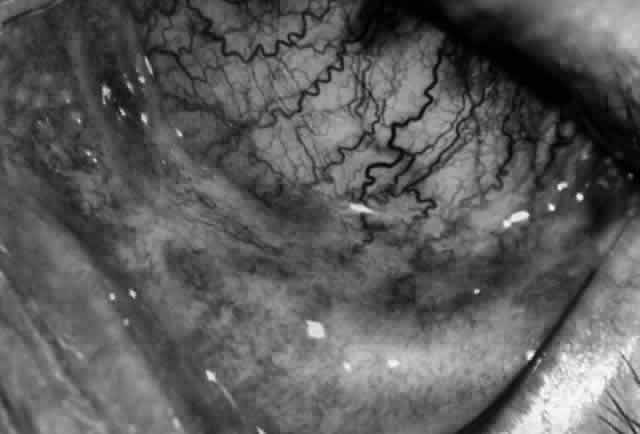

Clinically, the ocular disease in cicatricial pemphigoid (OCP) may present unilaterally in the form of a chronic, recurrent catarrhal conjunctivitis, but it eventually becomes bilateral. Subepithelial fibrosis is characteristic of stage 1 of OCP (Fig. 7). Stage 2 shows fornix foreshortening (Fig. 8), and symblepharon formation is the hallmark of stage 3 (Fig. 9). Stage 4, end-stage disease, is characterized by ankyloblepharon and surface keratinization (Fig. 10). Obstruction of the lacrimal ductules and meibomian gland ducts eventually produces an unstable tear film and progressive sicca syndrome, but it is to be emphasized that OCP is not a dry-eye syndrome until late in the disease course.20 Trichiasis and entropion occur because of the subepithelial fibrosis, with eventual keratopathy, corneal neovascularization, and corneal ulceration and scarring.20

Fig. 9. Stage 3 of an eye affected by cicatricial pemphigoid. The conjunctival “shrinkage” continued and a frank symblepharon developed.

Fig. 10. Stage 4 cicatricial pemphigoid. Progressive shrinkage of the conjunctiva resulted in extreme trichiasis and distichiasis and keratopathy, with compromise of meibomian ductules and lacrimal ductules and the production of a totally dry eye.